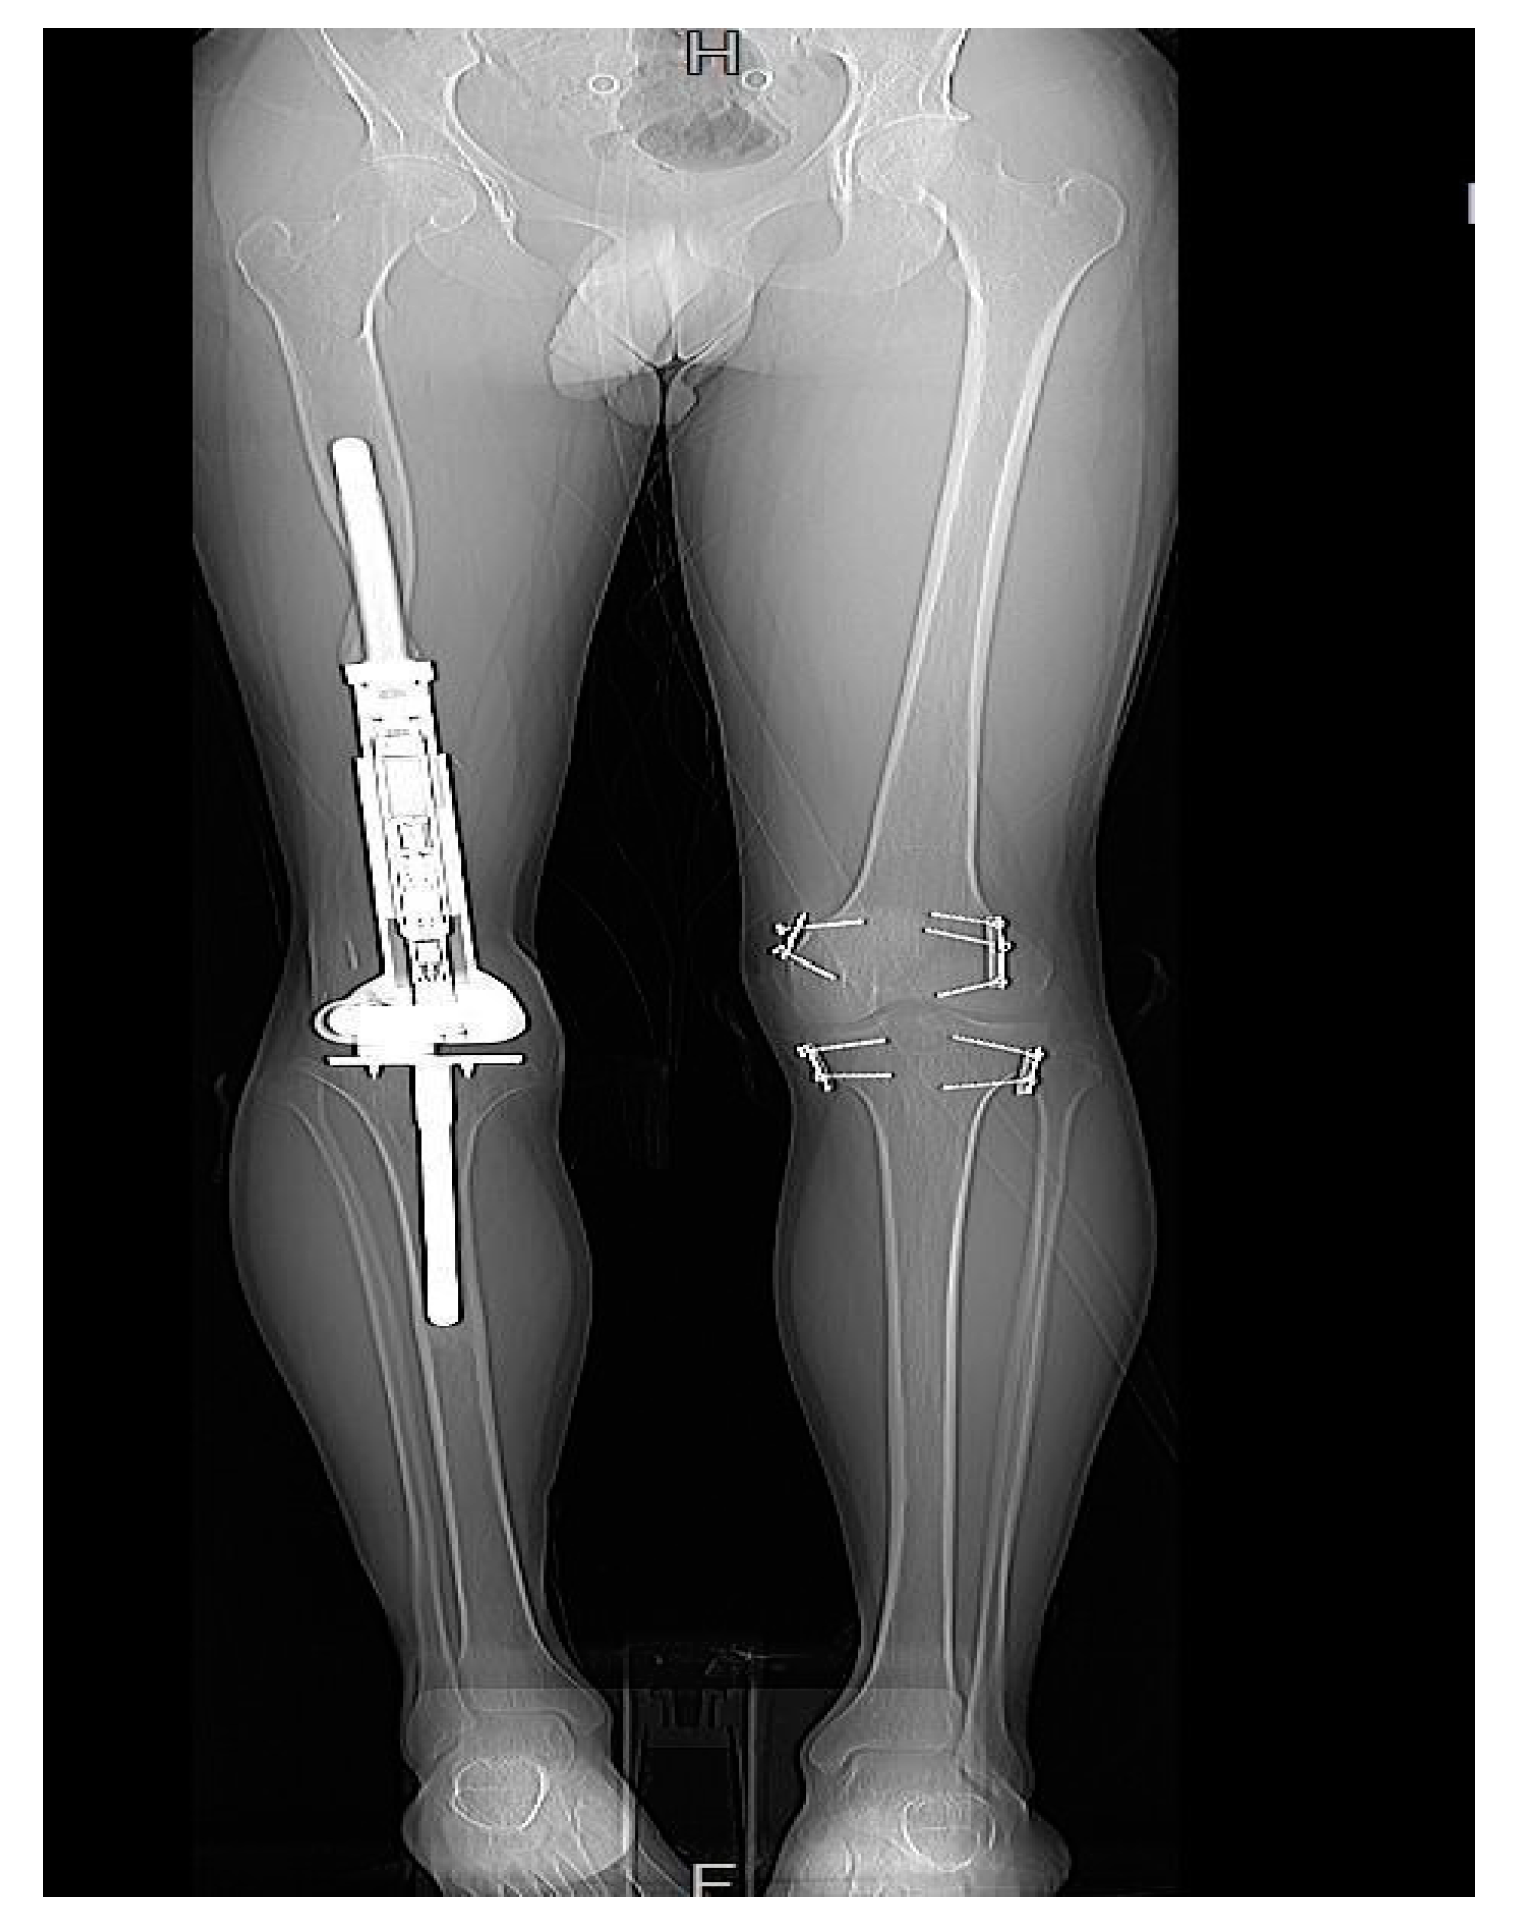

3.6. Need for Further Management

Patients with rotational and angular deformities did not necessitate management, as the deformities were tolerated well. Moreover, patients with an LLD of less than 10 mm demanded no further management. An LLD between 10 and 20 mm was managed solely by a shoe lift. However, an LLD of >20 mm, was treated on a case-by-case basis. Two patients required operative revision and serial elongation due to the anticipated growth potential of the contralateral leg. The remaining two patients were managed using epiphysiodesis of the contralateral distal femur and proximal tibia (Figure 7).

Figure 7.

Patient 3 had undergone EDFE using MUTARS® Xpand. However, due to an LLD of 37 mm, this patient required epiphysiodesis of the contralateral limb.